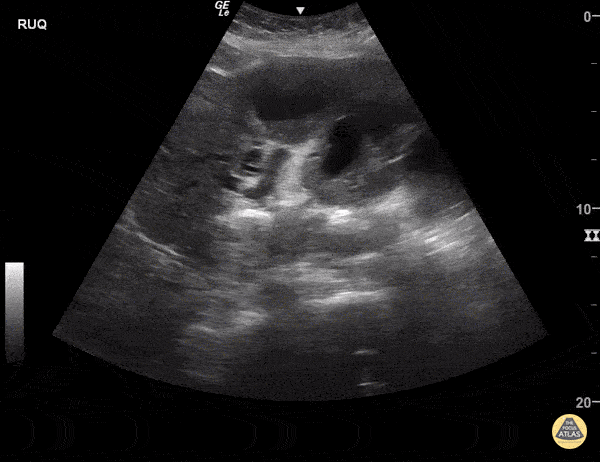

Cholangiocarcinoma with liver metastases and biliary sludge. Sukh Singh, MD